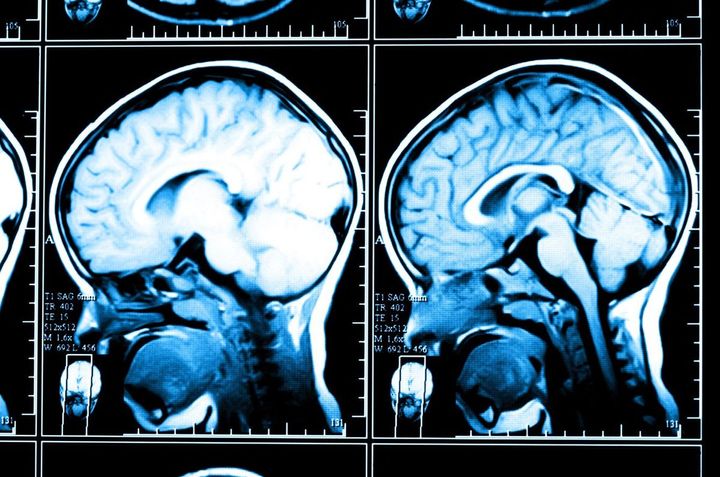

夫のMRIを撮った後、3年前の受診時に撮ったMRIと並べられた診察室で、医師から話があった。

頭部のCT画像

※写真はイメージです

「専門的なことはわかりませんが、素人目に見ても、3年前と脳の形が全然違うのがわかりました。医師は、病名は告げませんでしたが、話の内容から、手術で治る病気でないのはわかります。イヤな予感を抱えながら、神経内科の予約をして帰りました」